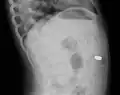

A coin seen on AP CXR in the esophagus

A coin seen on lateral CXR in the esophagus